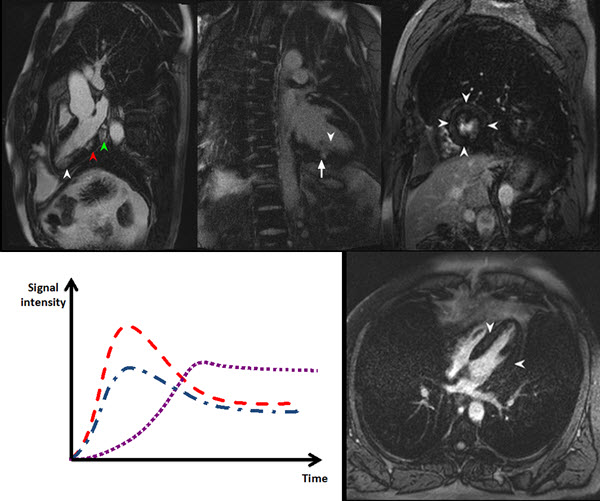

Acute Myocarditis Mri The Role Of Cardiovascular Resonance Case Report Cardiovascular Imaging In this review, we seek to provide insights on the role of cv imaging in the enrichment of clinical trial design by using techniques that can ensure precise risk stratification for efficient patient recruitment and. Case, a global, open access online journal, welcomes case reports where cardiovascular ultrasound is used to diagnose or help solve a clinical problem in humans. Case Report Cardiovascular Imaging.

Cardiac MRI. a Acquisition protocol includes assessment at rest and Case Report Cardiovascular Imaging Essential coverage of all aspects of cardiovascular imaging to improve diagnostic accuracy and advance clinical. In this review, we seek to provide insights on the role of cv imaging in the enrichment of clinical trial design by using techniques that can ensure precise risk stratification for efficient patient recruitment and. Case reports published in jcct. This case demonstrates the typical. Case Report Cardiovascular Imaging.